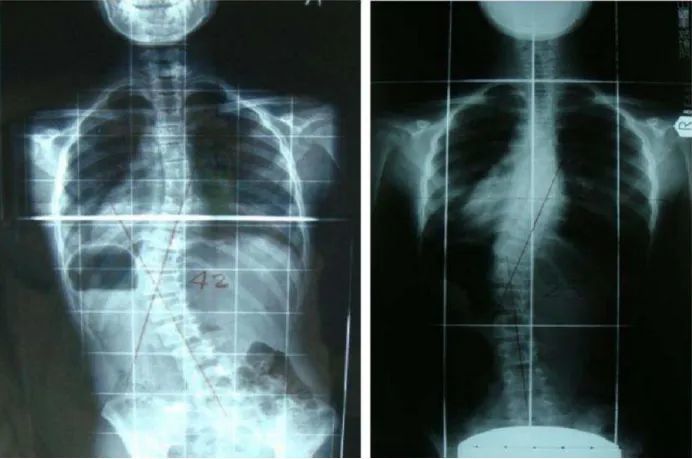

另一方面 , 月球与火星存在重力差异 , 而长期地重力环境将会给人类的脊椎造成巨大的压力 。 通过近些年来科学家对宇航员的身体机能的研究 , 人们已经认识到了太空环境会对人类产生的危害 。

即便地球的重量是火星上的2.6倍 , 人们也无法否定火星又是月球重力的2.4倍 , 相比之下 , 火星上的困难更容易克服 。